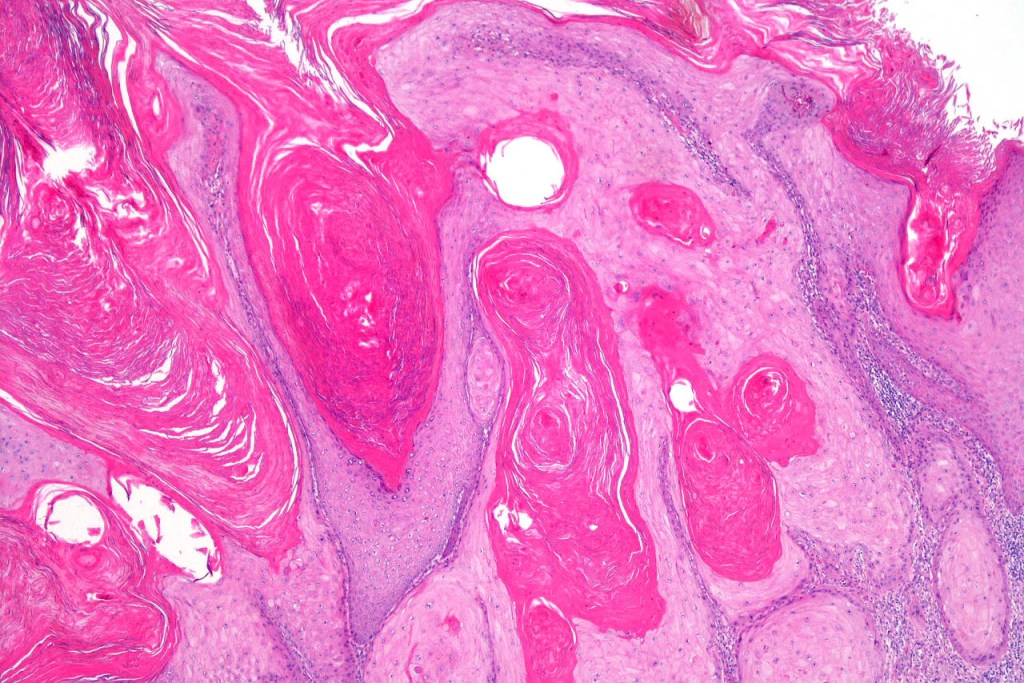

•Keratoacathoma (nowdays regarded as a variant of well differentiated squamous carcinoma) is characterized by a crateriform squamous epithelial lesion (dilated follicular infundibulum) with central keratin plug and adjacent collarette extending to the mid-dermis

•Well differentiated squamous epithelium often with a characteristic ground-glass appearance

•Only mild pleomorphism & basally located mitoses

•Neutrophil-rich microabscesses & necrosis

Below is a fascinating case shared on McKee Derm by Dr. James Simpson. There is an obvious keratoacanthoma but at the edge of the lesion there is marked atypia with nuclear enlargement and pleomorphism. This is also evident in the adjacent epidermis and in the deeper nests.